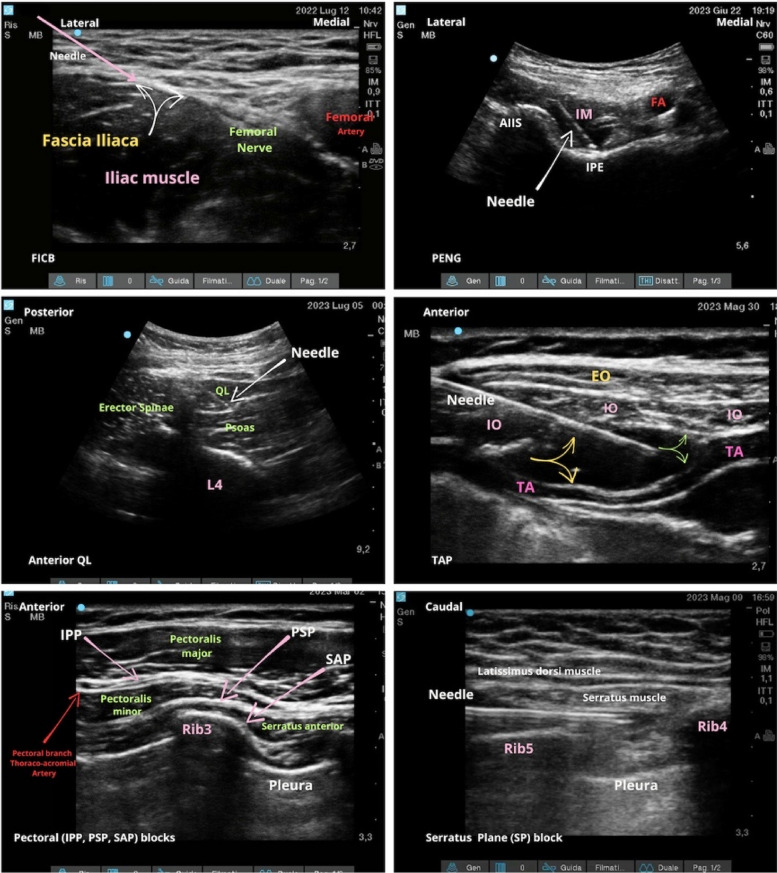

Background: Recent studies have unveiled the intricate and distinctive nature of fascia, no longer regarding it solely as a muscle container. Recent research highlights its complex innervation and structure, signifying its significance in chronic pain pathways.

Methods: We conducted a systematic literature search (updated on February 2024) to evaluate the role of fascial plane blocks in chronic pain treatment. All article types (randomized clinical trials, prospective and retrospective observational studies along with case reports and case series) were deemed eligible for inclusion if they referenced "fascial plane blocks" for the control of chronic pain conditions (persistent post-surgical, neuropathic, musculoskeletal-myofascial and cancer-related) and were published between 2010 and February 2024.

Results: The search revealed an increasing evidence in the literature for the implementation of fascial blocks in chronic pain management, although still heavily limited to case reports or series.

Conclusion: With the integration of ultrasound technology and a deeper understanding of their mechanisms of action, the fascial plane blocks continue to broaden their application also in chronic pain management, as a part of a multimodal strategy or as an alternative to conventional drugs or opioids.